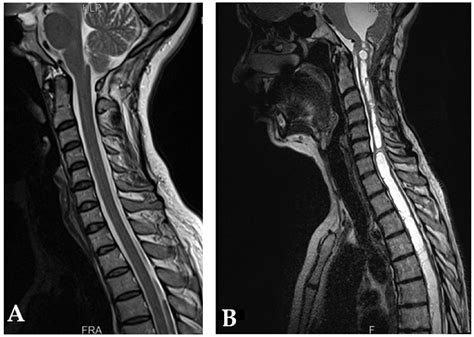

At its core, Cerebellar Tonsillar Ectopia describes the displacement of the cerebellar tonsils into the upper spinal canal. While often used interchangeably with Chiari malformation, it is important to note that the term "ectopia" typically refers to the physical descent of these structures. In many cases, this descent is identified incidentally during imaging studies like an MRI, performed for unrelated reasons such as persistent headaches or neck pain.

The primary concern with this condition is the crowding of the space at the base of the skull. Because the foramen magnum is a rigid, bony ring, any structure occupying space that should be reserved for fluid flow can lead to increased intracranial pressure. The degree of displacement is usually measured in millimeters, and while not every patient with this condition experiences debilitating symptoms, those who do often report complex neurological challenges.

Magnetic Resonance Imaging (MRI) Gold standard for visualizing the brain and spinal cord structure.

This includes physical therapy to improve neck stability, pain management medications for headaches, and monitoring via periodic MRIs. Lifestyle modifications, such as avoiding activities that involve heavy lifting or intense straining, can also help minimize pressure spikes.

When conservative measures fail to provide relief, a procedure known as a posterior fossa decompression may be recommended. During this surgery, the surgeon removes a small piece of bone at the back of the skull (and sometimes the top of the first cervical vertebra) to create more room for the cerebellum and restore normal CSF flow. This helps alleviate the pressure and allows the brain to function without the constant constraint of the bony environment.